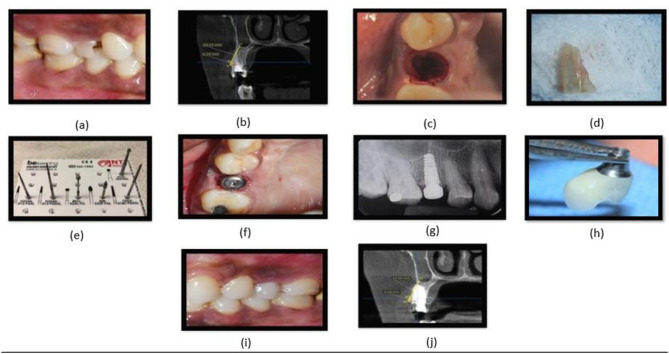

Purpose: The present study aimed to evaluate the appropriate protocol to be followed in the maxillary esthetic zone involving single dental implants by comparing three implant placement protocols: immediate implant placement (IIP) with and without the socket shield technique (SST) and delayed implant placement (DIP) in terms of dynamic alterations in hard and soft tissues and patient-related outcome measures (PROMS).

Materials and methods: A total of 75 patients were recruited for the study and randomly allocated to the SST, IIP, and DIP groups (25 each). They were subjected to Cone Beam Computed Tomography (CBCT) assessment pre-operatively, 6 and 12 months post-operatively to evaluate changes in Crestal Bone Thickness (CBT). Soft tissue changes were evaluated using the pink aesthetic score (PES) and visual analogue scale (VAS) to assess the pain threshold and patient satisfaction.

Results: There was a statistically significant difference in the mean reductions in crestal bone thickness (CBT) between and among the groups. The SST group demonstrated a significantly lower reduction in CBT (0.09) than the IIP and DIP groups, which showed a mean reduction in CBT of 0.18 and 0.50 at (p<0.01), respectively, at the end of 12 months. However, when the mean differences in PES between the groups were compared, there was a statistically significant difference for SST 13(2), IIP 10(2), and DIP 9(2) (p<0.01).

Conclusion: Socket shield technique could be technique of choice for IIP when buccal bone thickness is <1mm as demonstrated by less reduction in CBT and better PES at the end of 12 months than the IIP and DIP groups.